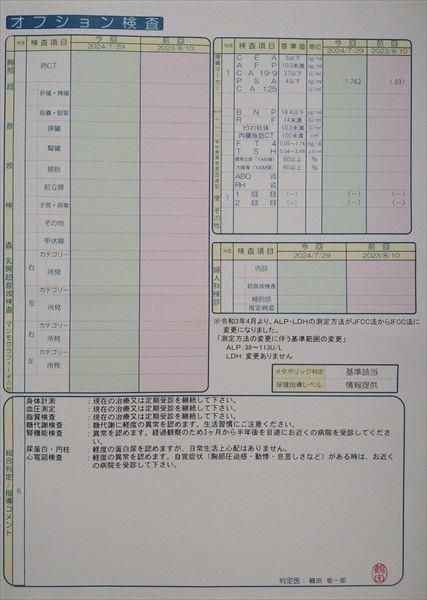

0109 24.7.29健康診断=pdf

0108 ①22.8.23荒尾市民病院=pdf ②2023-08-21健康診断結果.pdf 8/10(木)受診 荒尾市民病院

2024.18.14 荒尾市民病院 2023.08.10 荒尾市民病院

2024 PDF 2023 PDF